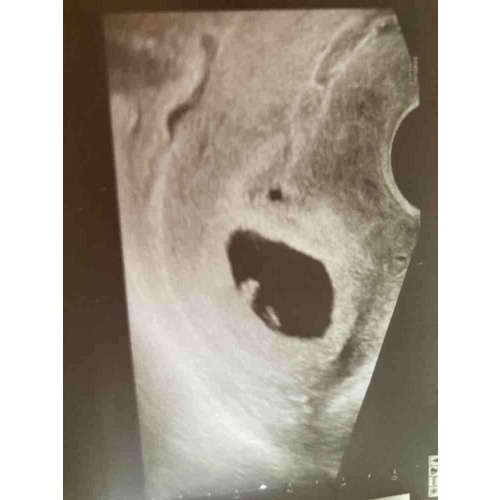

Vruchtzakje 6 Weken Miskraam. Hoe Lang Blijft Een Leeg Vruchtzakje Zitten Bij Een Miskraam? Ik ben afgelopen maandag voor nog een controle geweest (ruim een week na de miskraam) en toen was het vruchtzakje verdwenen Kreeg toen ook de boodschap: of buitenbaarmoederlijke zwangerschap, of wordt een miskraam, of je bent nog niet zo ver

Een miskraam bij 5 of 6 weken kan op verschillende manieren verlopen Nadat de miskraam volledig tot stand is gekomen of de curettage succesvol is uitgevoerd is de zwangerschap beëindigd en.

Een miskraam bij 5 of 6 weken kan op verschillende manieren verlopen Kreeg toen ook de boodschap: of buitenbaarmoederlijke zwangerschap, of wordt een miskraam, of je bent nog niet zo ver 'Ik wist niet hoe een miskraam bij zes weken eruit ziet' Een miskraam na 6 weken